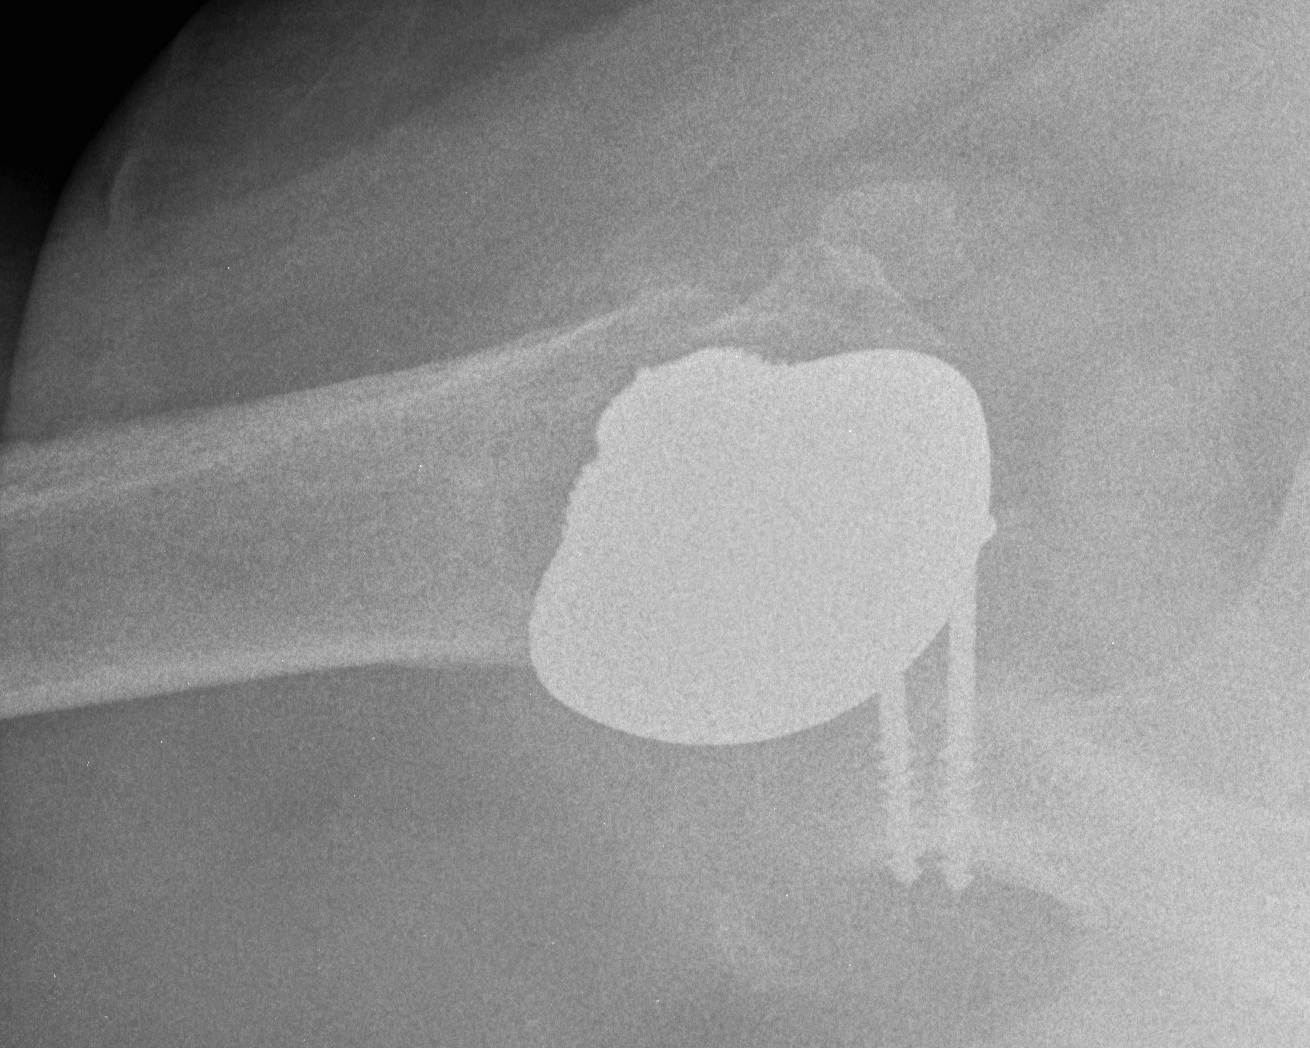

Reverse TSA +/- glenoid bone graft

Chronic locked with large Hill Sachs treated with rTSA + glenoid bone graft

Chronic locked with large Hill Sachs and normal glenoid treated with rTSA + glenoid bone graft